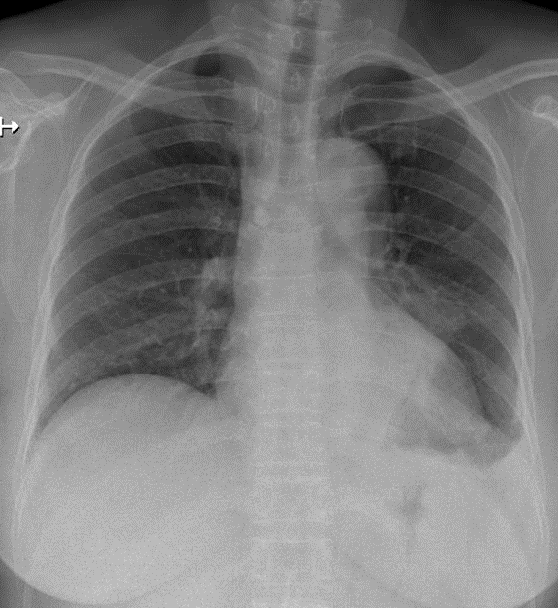

1-Tổn thương dạng khối mờ thùy dưới phổi (T) => U phổi 2-Tràn dịch màng phổi (T) 3-Cung động mạch chủ đóng vôi